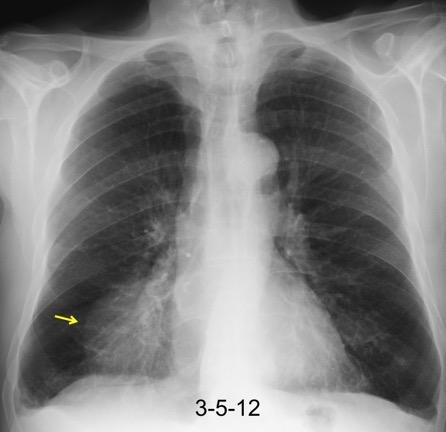

30 años

Borramiento de la banda PARA-aórtica por AdenoCa. de LII, no visible en 2005

Colapso de LII. TC: secreciones bronquiales.

Endoscopia tapón mucopurulento extraído

Borramiento parcial por Ca. epidermoide.